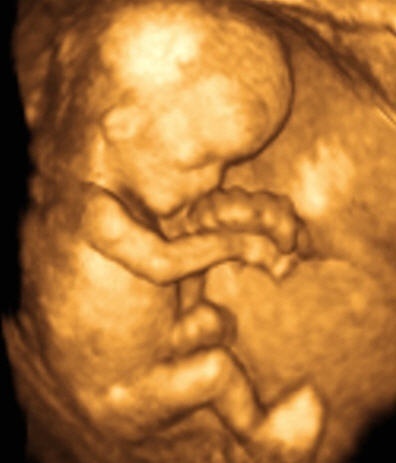

coucou les filles voila je sais que jai deja poster car je doute sur le sexe de mon bebe mais je voulez vous montrez une echo que jai trouvez sur le net elle est en 3d et de profil mais ressemble quand meme a la mienne donc le soit disant sexe ( garcon ) que mon gygy a vue mon je pense plus au cordon vue que ca fait vraiment comme les 3 boules comme sur celle en 3d ! vous en pensez quoi ??? merci

• Echographie-3D-11-semaines-image-réduite.jpg

Echographie-3D-11-semaines-image-réduite.jpg

30.9 KB · Affichages: 5,906

a 18 semaine de grossesse et si ont voit tres bien regarde sur celle en noir et blanc lendroit ou y a la fleche cest soit disant le zizi mais il me parait enormes si tu compare avec celle en 3d les 3 boules qui monte ca ressemble bien au cordon

oui pour celle en 3D cest le cordon apparremment mais a 18 semaine de grossesse tu es donc a 4 mois et demi on voit tres bien le sexe du bébé c'est vraiment rare que l'on se trompe